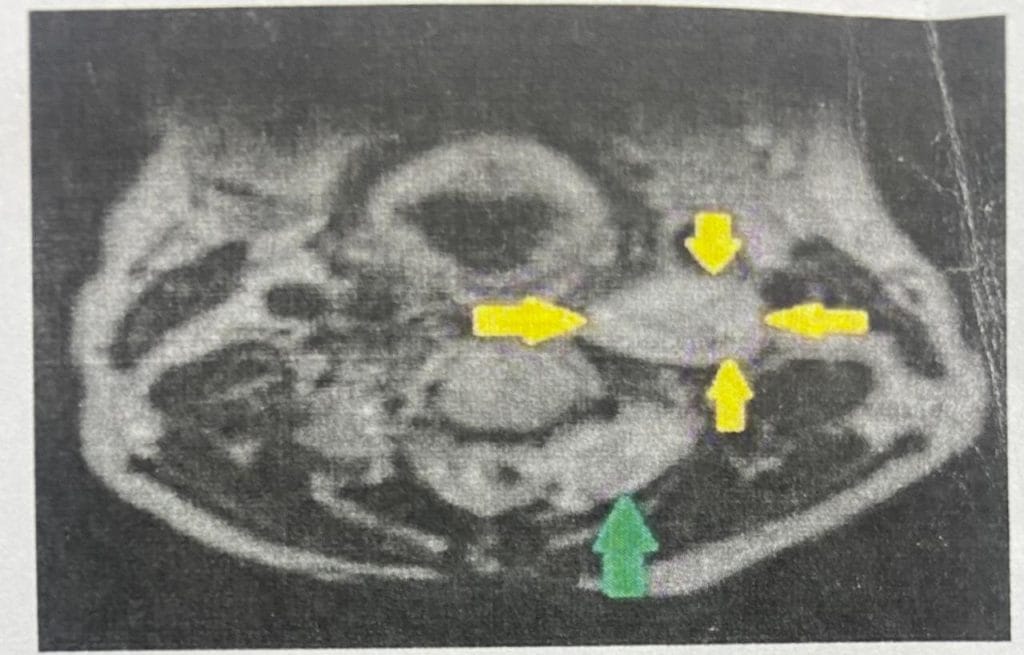

أجرى فريق طبي جراحي في مستشفى ابن سينا التدريبي ببغداد عملية نوعية لرفع ورم ليفي عصبي متعدد ممتد من الحبل الشوكي ( الفقرة العنقية ٣/٤)

حيث كانت هناك التصاقات مع الشريان السباتي الايسر